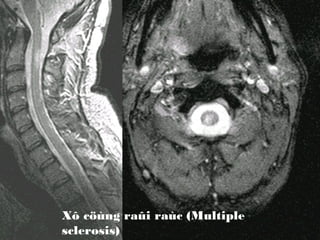

Xô cöùng raûi raùc (Multiple

sclerosis)

MS